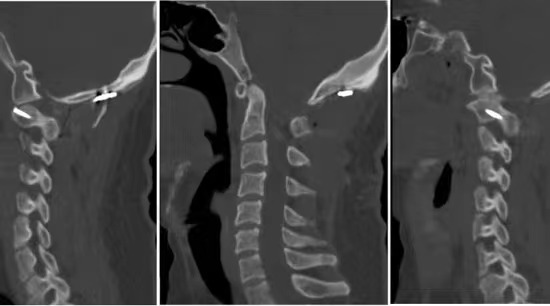

• 诊断:寰枢椎脱位、颅底凹陷、小脑下疝、脊髓空洞

• 影像: